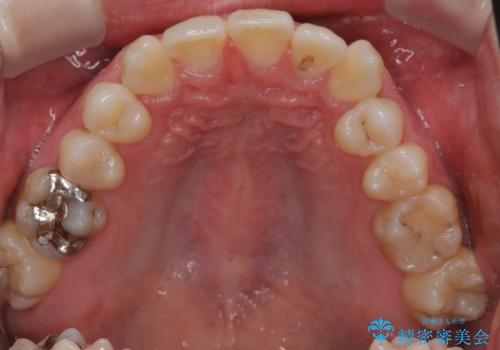

- 右上2番が欠損しており、歯並びをバランスよくしたいということで来院されました。

右上2番が欠損しているため、見た目と噛み合わせの両方のバランスを整えるために経過を追いながら必要な部位にゴム掛けをしました。

また矯正後、患者様の希望で

メタルインレーをセラミックインレーにやりかえさせていただき、さらに綺麗に仕上がりました。